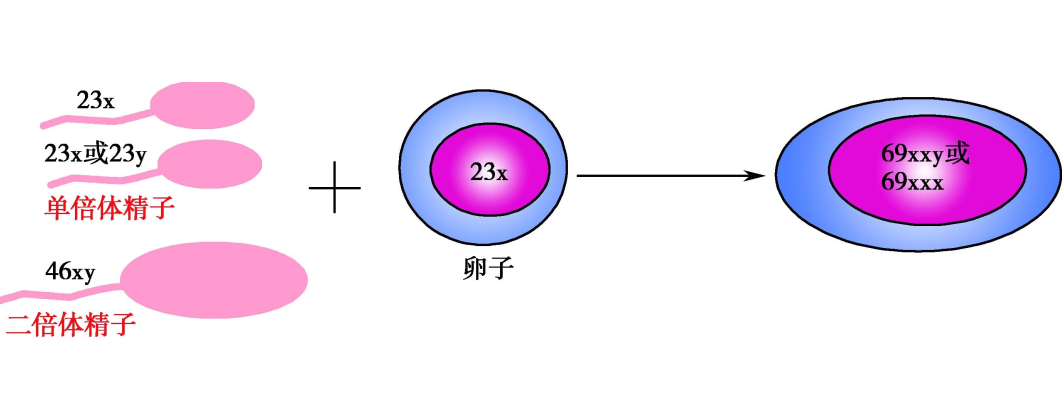

部分性葡萄胎的染色体核型90%以上为三倍体,合并存在的胎儿也为三倍体。最常见的核型是69,XY,其余为69,XX或69,XYY,系由一看似正常的单倍体卵子和两个单倍体精子受精或一个减数分裂缺陷的双倍体精子受精而成,所以一套多余的染色体也来自父方。多余的父源基因物质也是部分性葡萄胎滋养细胞增生的主要原因。另外尚有极少数部分性葡萄胎的核型为四倍体,但其形成机制还不清楚。

部分性葡萄胎受精示意图